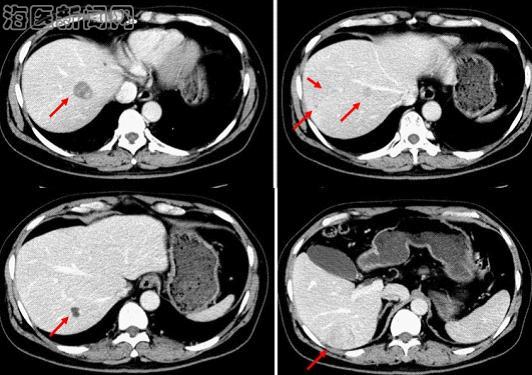

该名患者为老年男性,肝脏CT检查示6、7、8段出现多发占位,考虑原发性肝癌。但病人的体重较重,左半肝体积又很小,如行右半肝切除左半肝不能满足病人所需的最小肝脏体积,术后发生肝功能衰竭的风险极高。该病例的病灶位于右肝6、7、8段,若能保留5段则剩余肝脏能满足病人所需的最小肝脏体积,因此经过严密的术前讨论分析,肝胆外科贾长库主任选择了手术难度非常大的保留5段的规则性右肝三段切除。